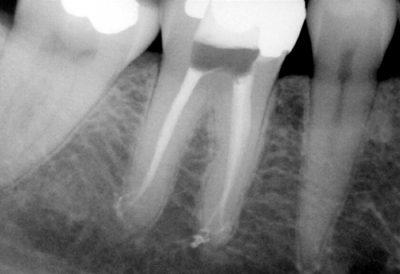

Un traitement de racine ou traitement endodontique consiste à traiter l’intérieur d’une racine

(par élimination du paquet vasculaire et nerveux appelé “pulpe”).

Il s’agit généralement d’une dévitalisation ou d’une désinfection (dent malade par abcès).

- Les obturer en compactant une gutta percha à chaud (caoutchouc étanche)